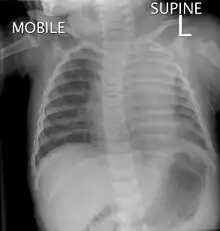

Cystic hygromas are increasingly diagnosed by prenatal ultrasonography. A common sign is a neck growth. It may be found at birth, or discovered later in an infant after an upper respiratory tract infection.[9]

Lymphatic malformations may be detected in the human fetus by ultrasound if they are of sufficient size. Detection of a cystic malformation may prompt further investigation, such as amniocentesis, to evaluate for genetic abnormalities in the fetus. Lymphatic malformations may be discovered postnatally or in older children/adults, and most commonly present as a mass or as an incidental finding during medical imaging.

Verification of the diagnosis may require more testing, as multiple cystic masses can arise in children.[10] Imaging, such as ultrasound or MRI, may provide more information as to the size and extent of the lesion.